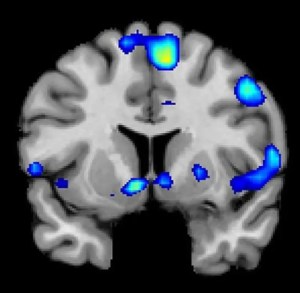

Με βάση τις σαρώσεις fMRI, οι ερευνητές διαπίστωσαν ότι ισχυρά πνευματικά συναισθήματα συνδέονταν με ενεργοποίηση στον πυρήνα, μια κρίσιμη περιοχή του εγκεφάλου για την επεξεργασία ανταμοιβής. Η μέγιστη δραστηριότητα σημειώθηκε περίπου 1-3 δευτερόλεπτα πριν οι συμμετέχοντες πατήσουν το κουμπί και επαναλήφθηκαν σε καθεμία από τις τέσσερις εργασίες. Καθώς οι συμμετέχοντες βίωναν μέγιστα συναισθήματα, οι καρδιές τους χτυπούσαν γρηγορότερα και η αναπνοή τους βάθυνε.

Εκτός από τα κυκλώματα ανταμοιβής του εγκεφάλου, οι ερευνητές διαπίστωσαν ότι τα πνευματικά συναισθήματα που η θρησκευτική πίστη ενεργοποιεί, συσχετίστηκαν με τον μεσαίο προμετωπιαίο φλοιό, που είναι μια σύνθετη περιοχή του εγκεφάλου που ενεργοποιείται από εργασίες που περιλαμβάνουν αποτίμηση, κρίση και ηθική συλλογιστική, καθώς και περιοχές του εγκεφάλου που σχετίζονται με την εστιασμένη προσοχή.